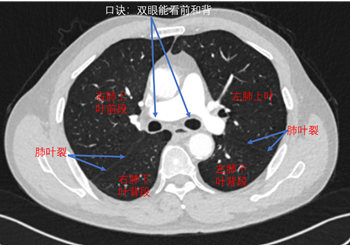

看见左右主支气管(双眼)层面:右肺上叶前段和右肺下叶背段,左肺上叶和